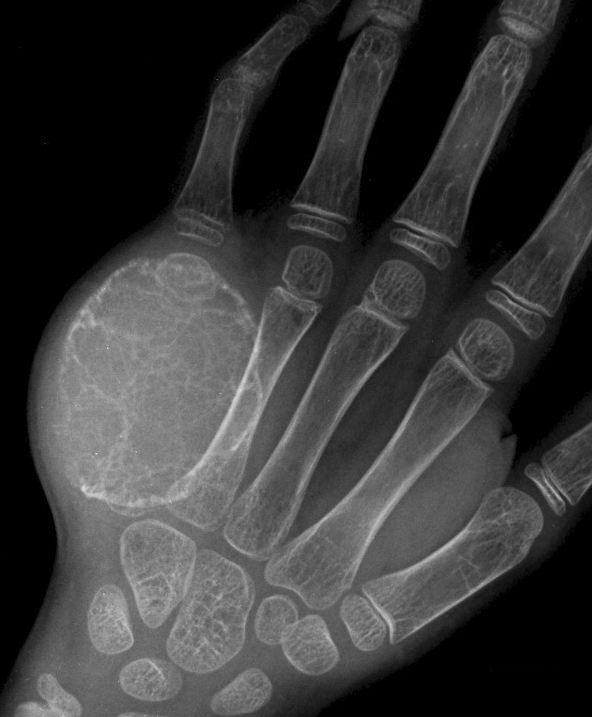

骨和软组织钙化

瘤软骨钙化

瘤软骨常表现为环状钙化, 是诊断软骨类肿瘤较为可靠的影像学征象。环状钙化形成于环状软骨、以及软骨小叶边缘的软骨基质。钙质沉着可呈小点状、小条状、半环状或弧形;亦可浓密相连、重叠呈菜花状。钙化环的形态和密度可反映瘤组织分化程度, 通过观察钙化环的形态和密度,有助于良恶肿瘤的鉴别。良性瘤软骨之瘤细胞分化好、生长缓慢、血供充分, 钙化环完整,密度高, 边缘清楚。良性软骨类肿瘤如骨软骨瘤(图 35)、软骨母细胞瘤(图 36)、内生软骨瘤(图 37)等均可于瘤组织内发生环形钙化。恶性瘤软骨则呈密度淡薄, 边缘模糊的不规则钙化,恶性骨肿瘤的环形钙化,最多见于软骨肉瘤(图 38),其次是骨肉瘤。CT 是发现肿瘤内软骨钙化最为敏感的检查方法。

图 37.瘤软骨钙化:内生软骨瘤